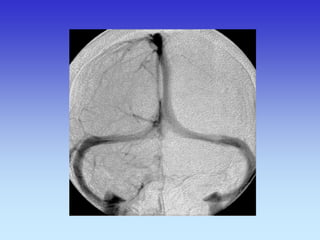

METODE PRIKAZA KRVNIH ŽILA

•UZ-DOPPLER

•DSA

•CTA

•MRA

VASKULARNA OPSKRBA WILLIS-ijev prsten

a. cerebri ant.

a. cerebri media

a. cerebri post.